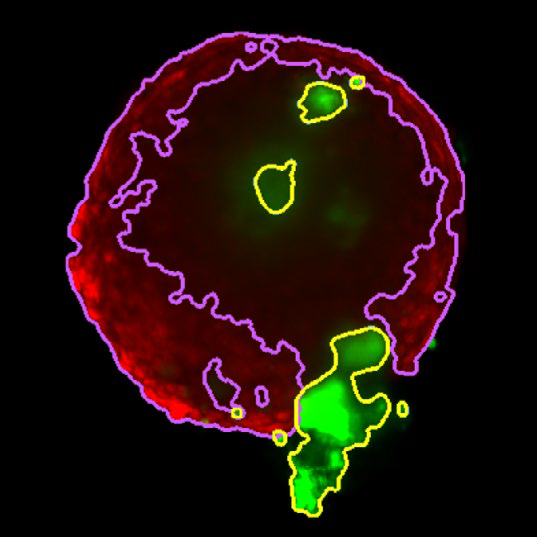

Figure 3. Z slice of the tumor microtissue treated with 0.05 % DMSO - tumor (yellow region) and fibroblast (purple region) are recognized separately in 3D. Image Credit: Yokogawa Life Science

Figure 4. Z slice of the tumor microtissue treated with 5 μM Lapatinib - tumor (yellow region) is decreased significantly compared to the one treated with 0.005 % DMSO. Image Credit: Yokogawa Life Science

Tumor spheroids were created by seeding an Akura™ 384 plate with a monodispersed mixture of GFP-expressing NCI-N87 (gastric carcinoma) and RFP-expressing NIH3T3-L1 (murine fibroblast) cells, which spontaneously formed spheroids through scaffold-free self-assembly over several days. After spheroid formation, selected wells containing tumor spheroids were treated with DMSO at 0.05, 0.5, or 5.0 μM Lapatinib for six days. The images were analyzed in 3D, with NCI-N87-GFP (tumor) and NIH-RFP (fibroblast) identified separately, and the volume of each spheroid measured.